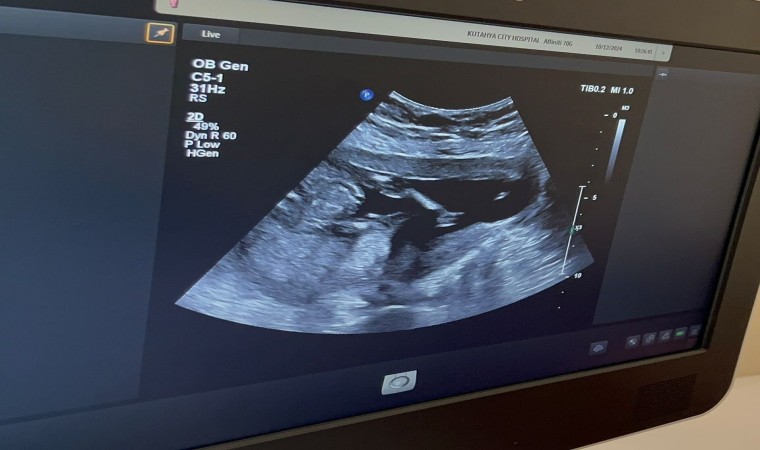

Amniyosentez, gebelik sürecinde bebeğin içinde bulunduğu amniyotik sıvıdan örnek alınarak yapılan teşhis testidir. Bu işlem, genetik hastalıkların, kromozomal anomalilerin veya enfeksiyonların tespit edilmesi için gebeliğin 15-20. haftalarında gerçekleştirilir. Ultrason eşliğinde yapılan bu işlem sırasında annenin karnından ince bir iğne yardımıyla amniyotik sıvı alınır. İşlem steril şartlarda, anne ve bebeğin güvenliği gözetilerek tamamlanır.

Kütahya Şehir Hastanesinde ilk amniyosentez işlemini gerçekleştiren Dr. Fatih Akkuş, Kütahya’da görev yapmaktan mutluluk duyduğunu belirterek şu açıklamalarda bulundu: "Hastanemizde amniyosentez işleminin uygulanmaya başlanması, bölgemizdeki anne adaylarının prenatal tanı yöntemlerine erişimini kolaylaştırmak açısından önemli bir adımdır. Bu işlem, genetik hastalıkların ve anomalilerin tespiti açısından büyük bir öneme sahiptir. Gebelik sürecinde anne ve bebek sağlığını ön planda tutarak çalışmaya devam edeceğiz."